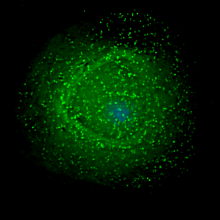

The new research is based on how the virus disguises itself from the human immune system and disrupts that system’s ability to communicate effectively. The virus accomplishes this by stealing cholesterol from the “first responder” cells called plasmacytoid dendritic cells (pDCs). These cells normally signal T-cells, the body’s heavy artillery, to defeat invaders. Instead, the AIDS virus “reprograms” pDCs to become hyperactive, which in inhibits the body’s ability to fight off the virus.

This new technique removes that cholesterol envelope from the virus, leaving the virus more or less defenseless. Researchers say that in their laboratory experiments, when the cholesterol shield is removed, the immune system attacks and neutralizes the diseases as if it were any other foreign body. It should be noted that the type of cholesterol used by the virus and targeted by the researchers is different than the “bad” cholesterol that causes heart problems.